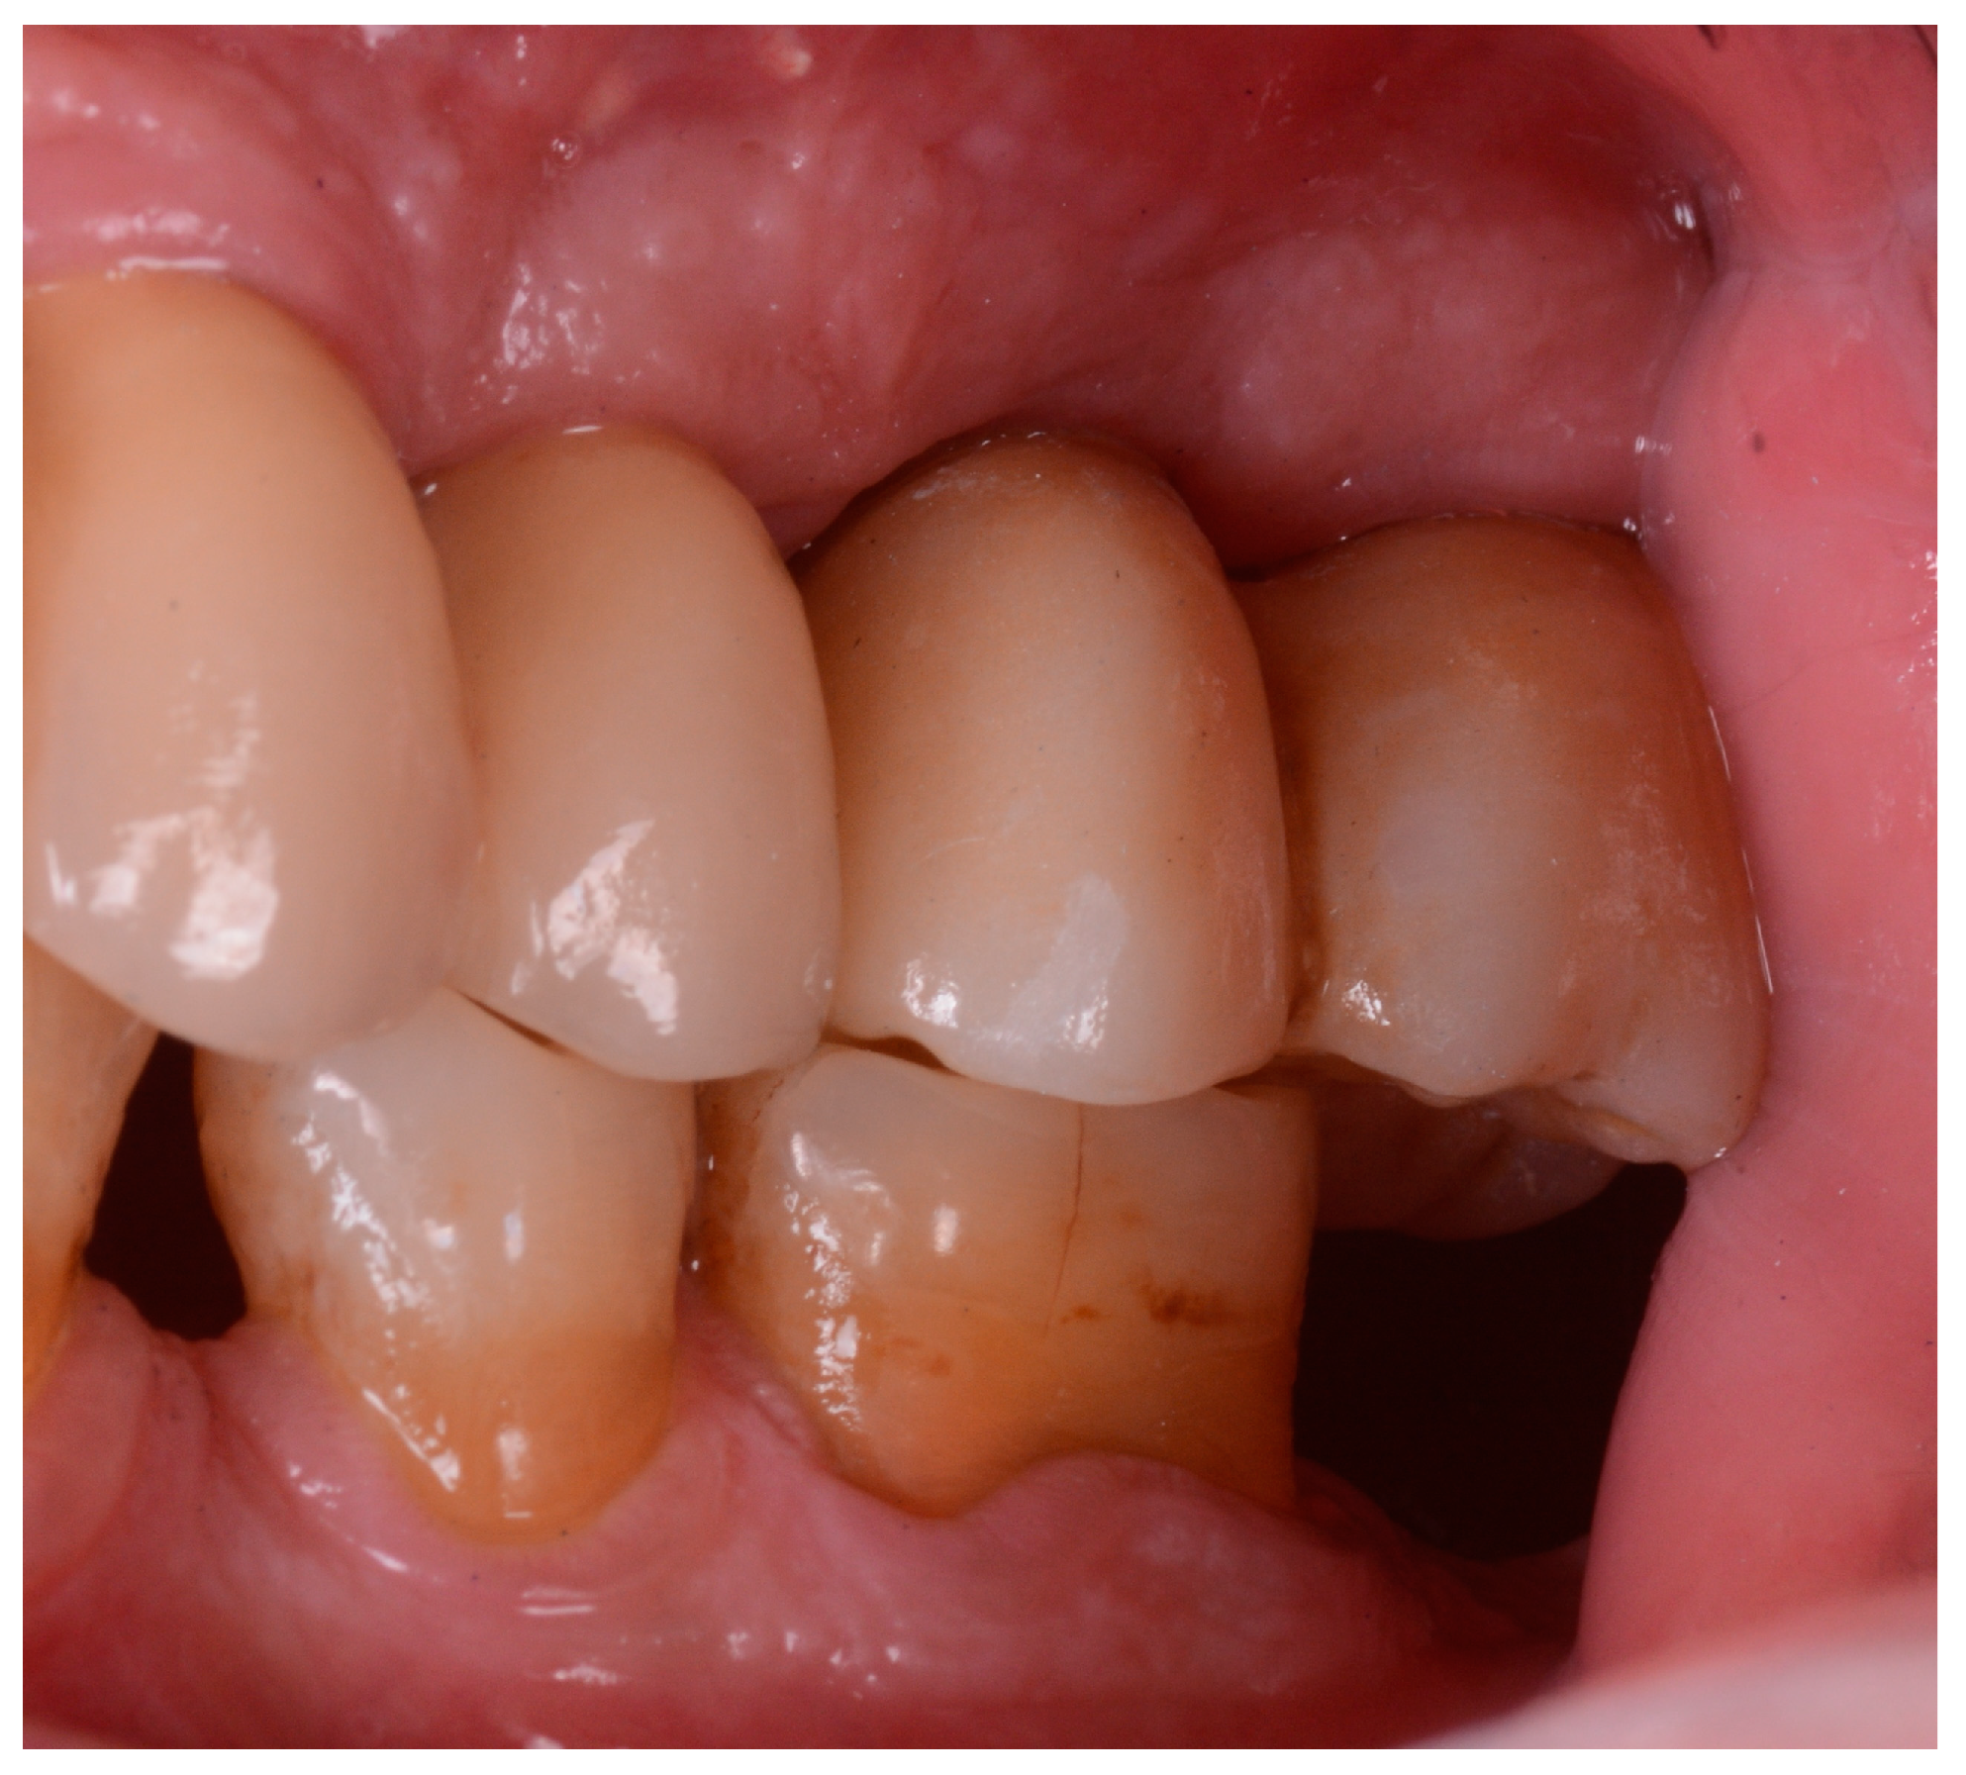

Figure 2 and Figure 3 illustrate the case conclusion, featuring an X-ray of the prosthetic rehabilitation after the extraction of the implant and neighboring teeth, along with an image of the completed prosthesis.

Figure 3.

Clinical observation after implant retrieval and rehabilitative restoration.